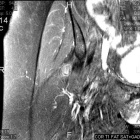

60 year old female presents for further evaluation after a mass was noted during workup related to treatment of a scalp melanoma in situ.